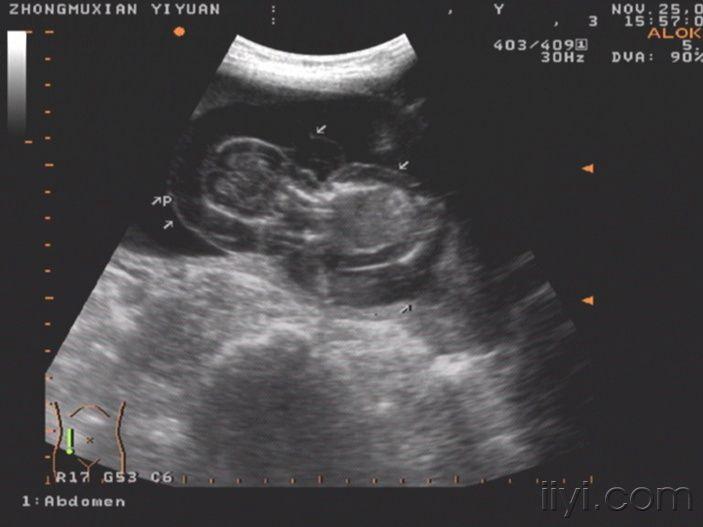

这个胎儿穿上了“太空衣”(典型胎儿水肿图片,值得分享!)

一位32岁经产妇,孕20周前来检查,发现胎儿被一层透明的膜状物包绕,从头颅到肢体,考虑胎儿水肿综合症!